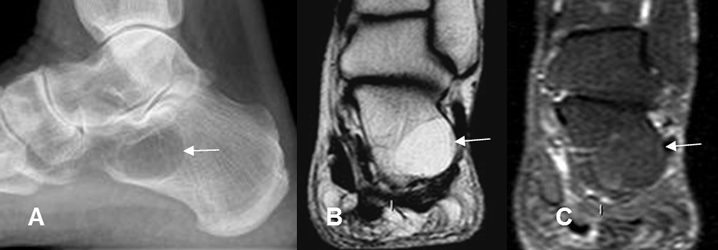

Fig 168 A. Lipoma intraoseo.

A: Rx lateral. Imagen redondeada, de bordes definidos y algo escleróticos, en la parte anterior del calcáneo, compatible con lesión benigna.

B: RM coronal en T1 y C: RM sagital en STIR. La lesión es hiperintensa en T1 y suprime en STIR, correspondiendo a lipoma.